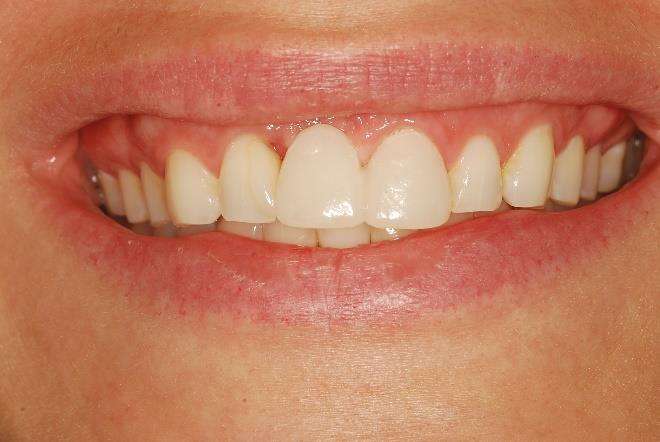

Fig. 3: Temporary Crown Seated Over the Implant

We first detoxify the implant surface, then add bone graft material enhanced with growth factors and cover it with a protective membrane to encourage new bone formation (Fig. 2). Four millimeters of bone can often be regenerated to shield the implant (Fig. 2). Throughout, a temporary bridge maintains aesthetics and function by seating over the site (Fig. 3).